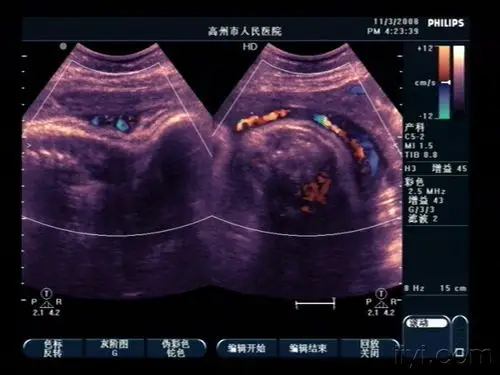

典型脐带绕颈(2周) - 超声医学讨论版 - 爱爱医医学论坛